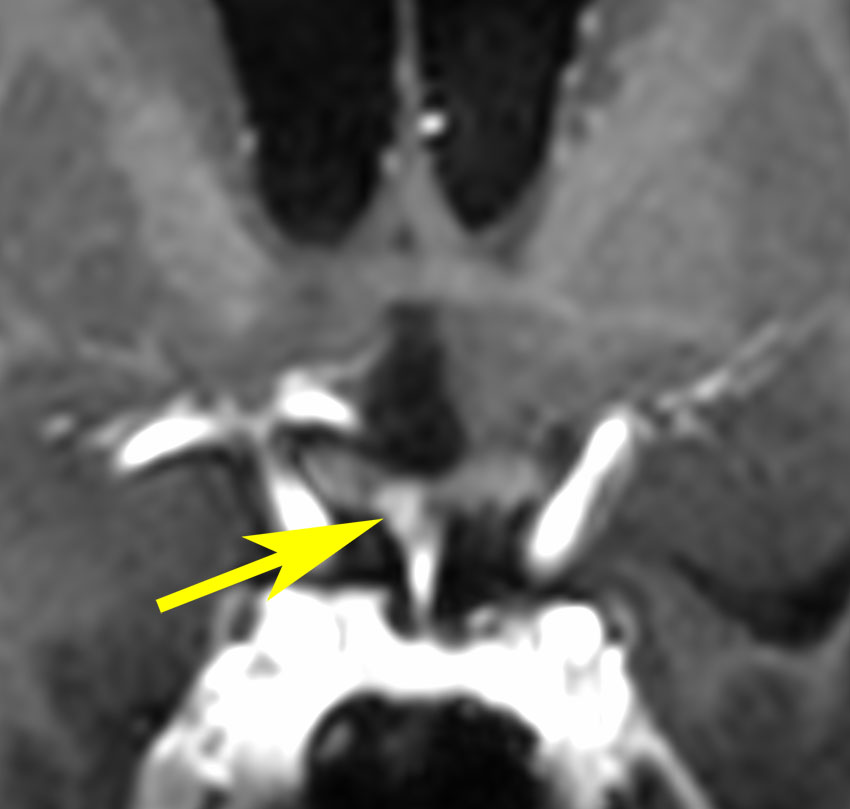

軽度の複視のみで発症した20代前半男性です。右上のように松果体腫瘍の前に割れ目が入るように第3脳室があり,両側視床に浸潤するために軽度の視床浮腫があり,ガドリニウムで強く増強され一部にのう胞があります。これだけでもgeriminomaにかなり特有の所見です。さらに,灰白隆起(矢印)のところに小さな神経下垂体germinoma腫瘍があります (bifocal tumor)。HCGは測定限界以下,AFP 2.5で,水頭症はありません。全ての臨床所見がgerminomaであることを示しています。

生検病理診断をしないでICE化学療法を1コース終えた後の画像です。腫瘍は消失しています。これでgerminomaであることが確認できたので,ICE化学療法を2コース追加して,25.2グレイの全脳室照射をして治療を終了しました。